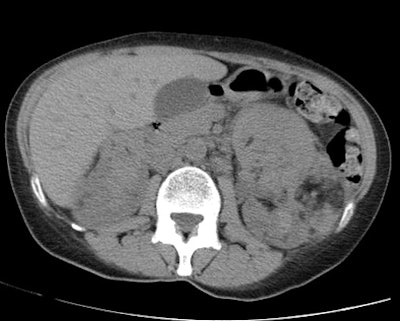

CT was performed and demonstrated multiple cysts throughout the lungs. The pneumothorax was noted to be loculated and predominantly in the lower portion of the right hemithorax.

Fat containing lesions were noted in both kidneys consistent with angiomyolipomas. Subsequently, it was learned that the patient had a history of lymphangioleiomyomatosis and had a prior pleurodesis.